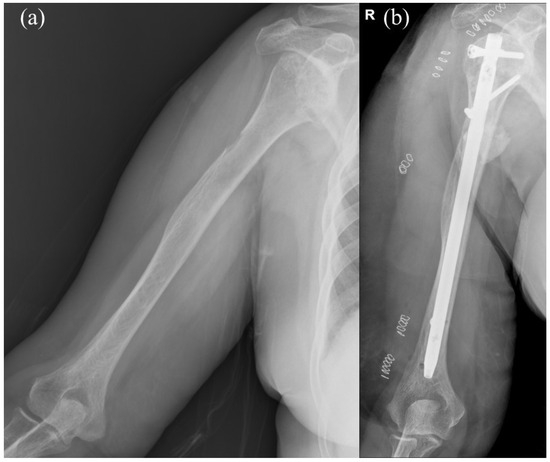

On the other hand, INF is a minimally invasive surgery with small incision wounds and is the favored surgical techniques for PHSF due to lower blood loss, decreased surgical time and better biomechanical stability (Figure 2). However, shoulder complications have been reported with INF, including rotator cuff damage, nail protrusion and shoulder impingement, leading to deteriorating quality of life for late-stage cancer patients.

Figure 2. (a) Preoperative image of a case with impending pathological fracture of right humeral shaft. (b) Intramedullary nail fixation with cement augmentation and bone curettage were performed for the impending pathological humeral shaft fracture. Letter “R” in the figure are referred to as right.